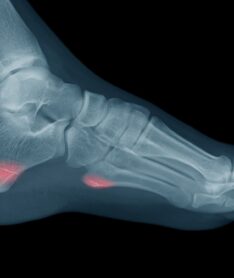

Initial treatment should include the RICE method (Rest, Ice, Compression, and Elevation). Your doctors at Professional foot and Ankle Center may recommend use of ankle brace or boot/cast immobilization. X-rays may be necessary to rule out fractures.

Normally, patients return to full activities by 6-8 weeks. If the ligaments of the inside part of the ankle are affected as well, recovery time may take 3-6 months. If pain and instability to the ankle persists, and conservative care (includes RICE, immobilization, physical therapy) fails for more than 6 months, surgical tightening of the ankle ligaments may be recommended.